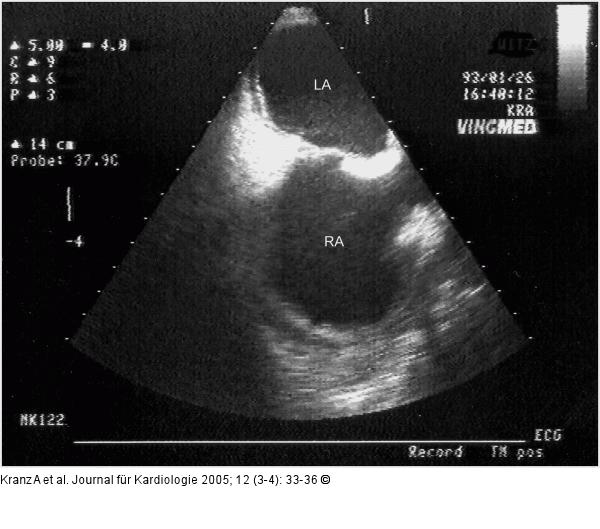

Abbildung 10a-b: Postoperative Veränderungen |

Abbildung 10a

Abbildung 10a-b: Postoperative Veränderungen